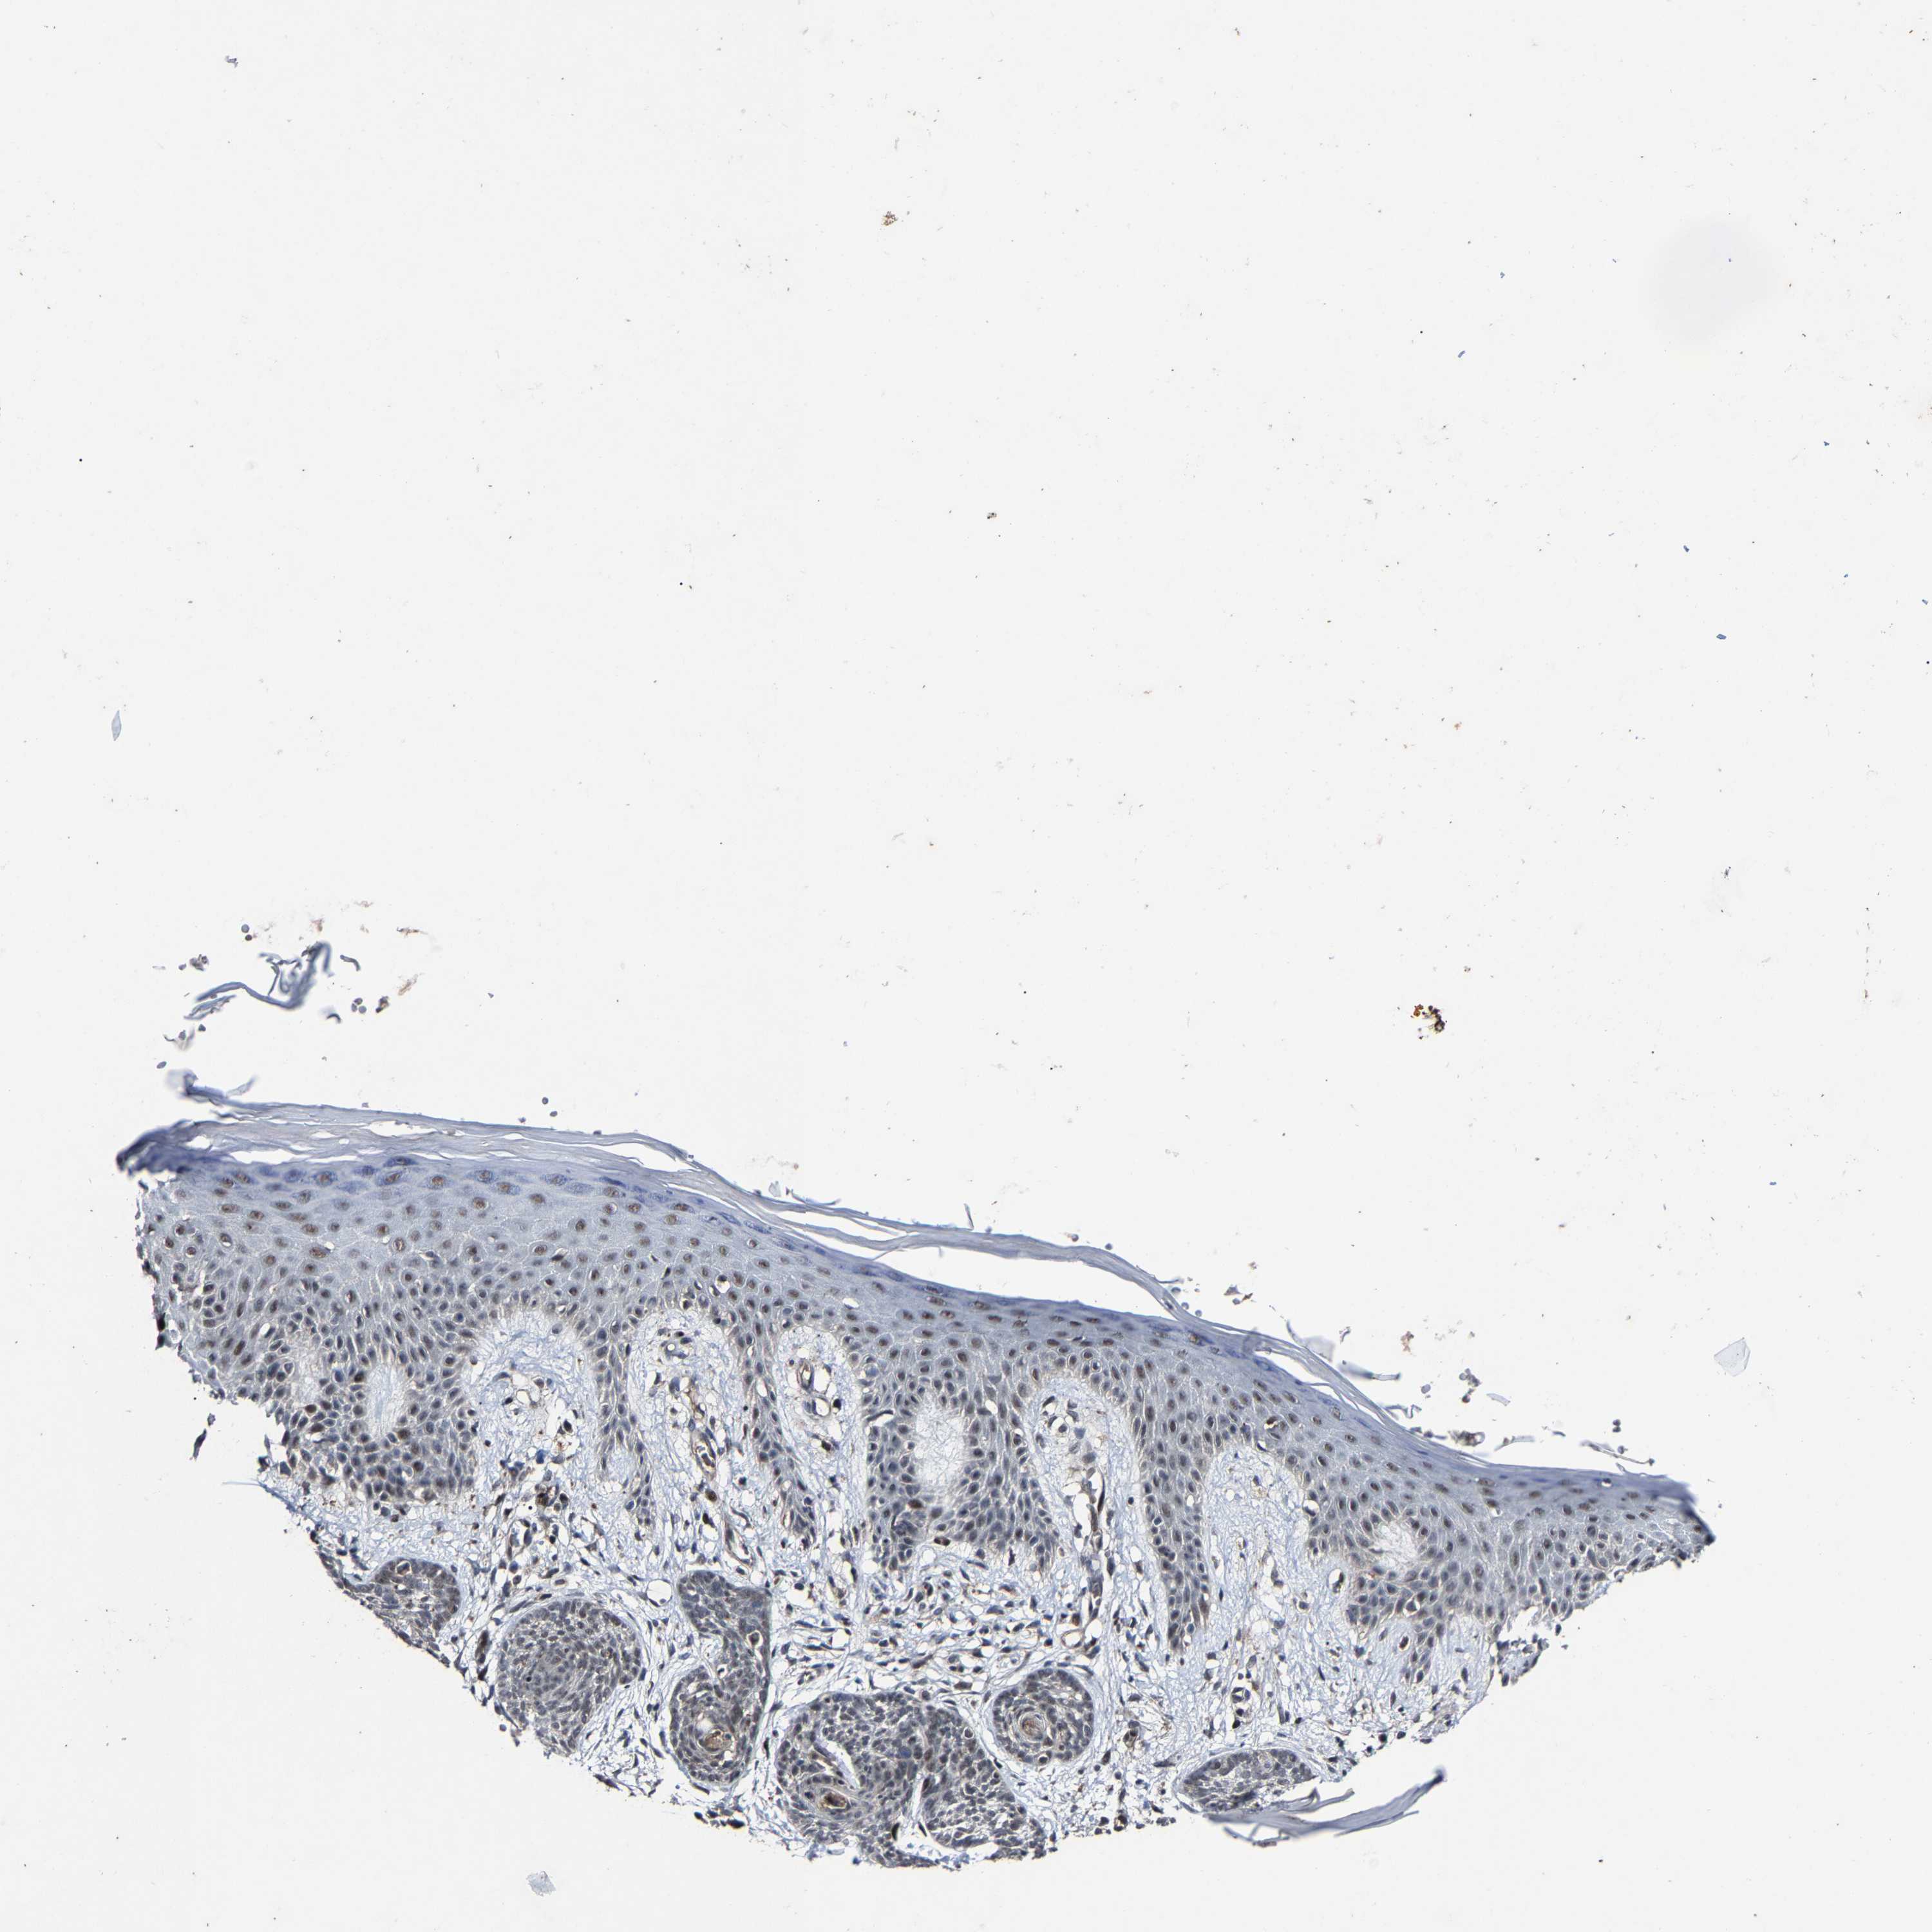

SKIN CANCER - Protein expressioni

A mouse-over function shows sample information and annotation data. Click on an image to view it in a full screen mode. Samples can be filtered based on level of antibody staining by selecting one or several of the following categories: high, medium, low and not detected. The assay and annotation is described here.

Antibody stainingi

Antibody staining in the annotated cell types in the current human tissue is reported as not detected, low, medium, or high, based on conventional immunohistochemistry profiling in selected tissues. This score is based on the combination of the staining intensity and fraction of stained cells.

Each image is clickable and will lead to virtual microscopy that enables deeper exploration of all samples and also displays staining intensity scores, fraction scores and subcellular localization as well as patient and tissue information for each sample.

Antibody HPA020116

Staining

High

Intensity

Strong

Quantity

>75%

Location

Nuclear

Squamous cell carcinoma in situ, NOS